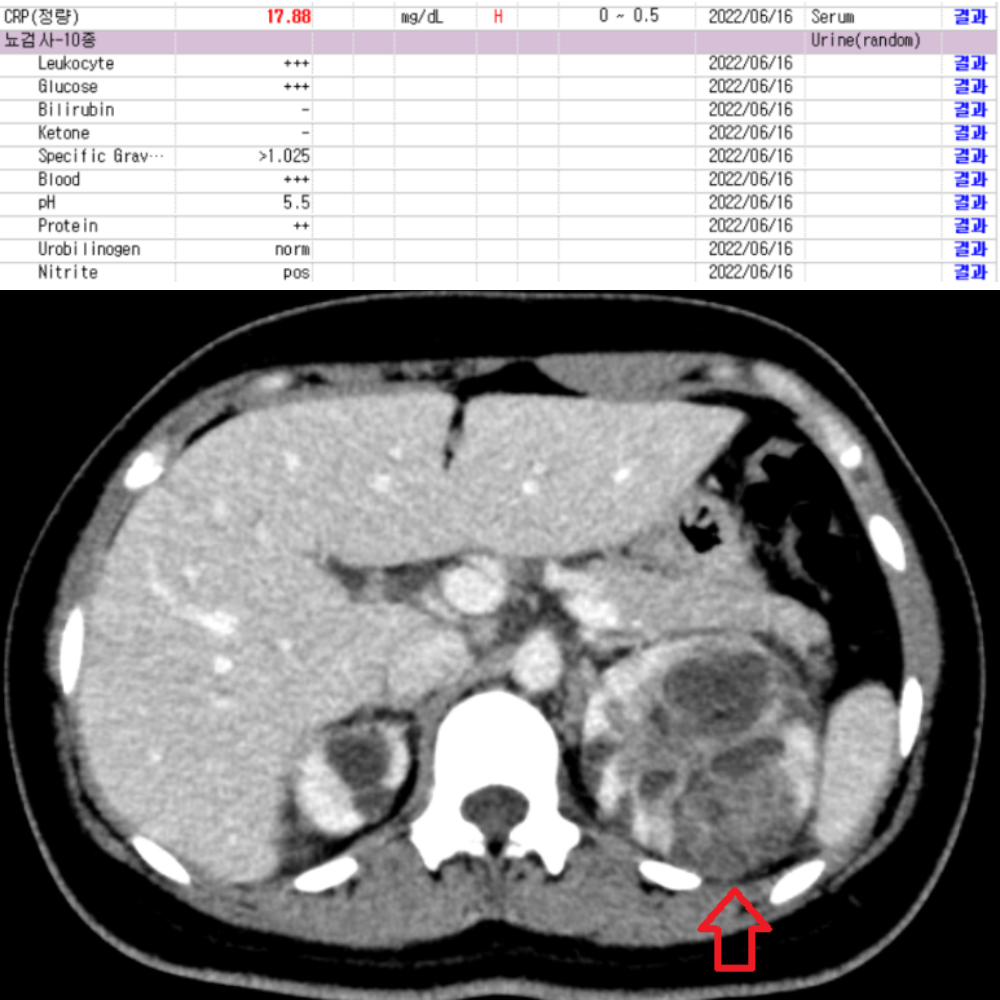

✔ 아랫배 통증과 함께 구토, 식욕 저하, 설사, 소변 이상이 있다

게실염, 충수염, 하복부통증 증상의 원인을 정확하고 신속하게 진단합니다.

게실염, 충수염, 하복부통증에 통해 관련 사례를 확인하실 수 있습니다.